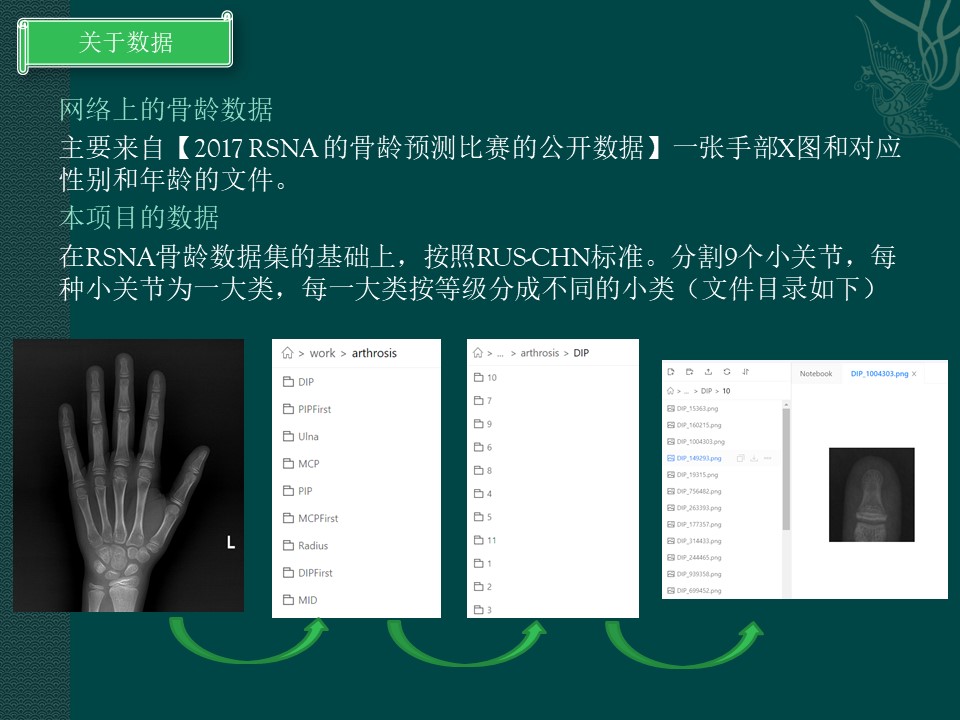

关于数据